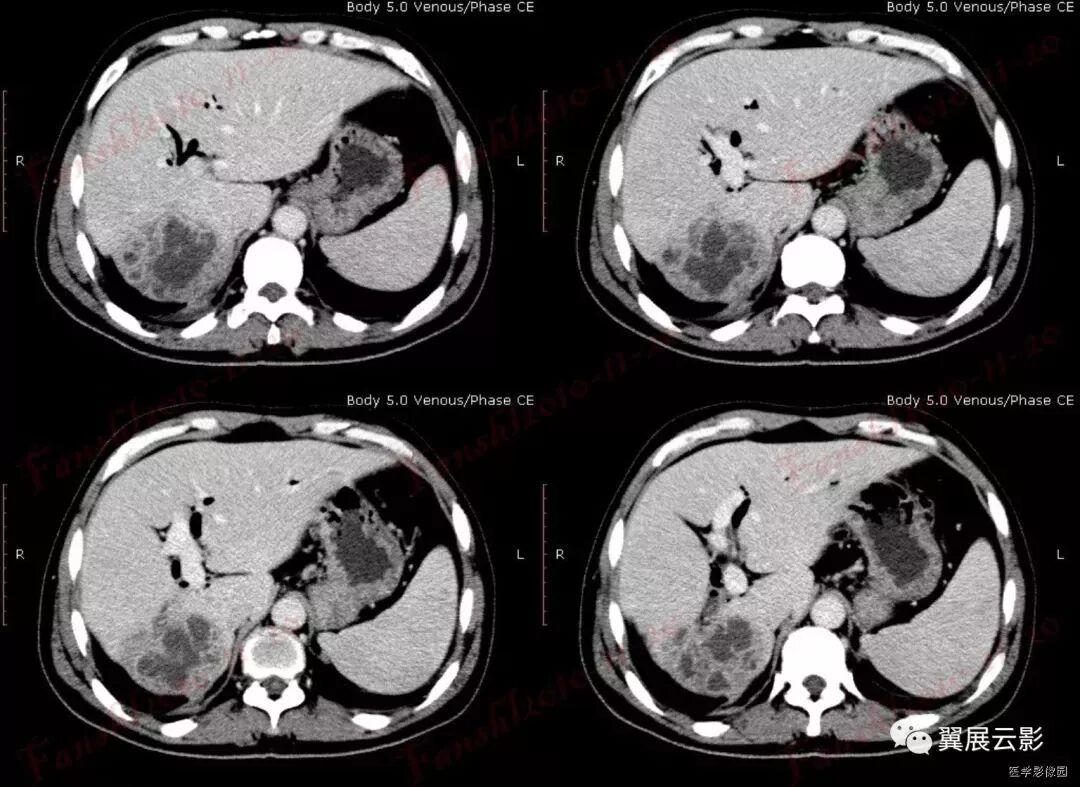

有多个名称,分别是:环靶征;双靶征;环征;双环征;三环征等。肝脓肿CT增强扫描的典型表现,因呈靶环状而得名。表现为肝内囊样低密度肿块病灶,边缘多数较模糊,脓肿周围往往出现不同密度的环形带(环征或靶征),增强扫描脓肿壁呈不同程度的环状强化,脓肿壁可为单环、双环或二环。

靶征是肝脓肿的典型征象,是脓肿形成期的表现。此期脓腔液化坏死彻底,脓肿壁可为单环,双环或三环,单环代表了脓肿壁,其周围水肿不明显;双环的内环代表脓肿壁,外环代表周围水肿带;三环表明脓肿壁由三层构成,外层(中环)为纤维肉芽组织,强化最明显,内层(内环)由炎性组织构成,强化不如外层纤维肉芽组织。肝脓肿靶征的出现代表着一定阶段病变的病理过程,为肝脓肿的特征性表现,对诊断很有价值。

大多数学者把肝脓肿的脓肿形成期CT表现认为是典型表现,表现为肝内囊样低密度肿块,病灶边缘多数较模糊,脓肿周围往往出现不同密度的环形带(环征或靶征),增强扫描脓肿壁呈不同程度的环状强化;少数患脓肿内出现气体,此时可肯定诊断。

增强扫描使病灶内部结构、病灶边缘与正常肝组织的关系显示得更清楚。门脉期可显示肝脓肿较典型的CT征象,为典型三层病理改变增强后的CT表现,中心坏死区无强化,中间层为介于液化坏死区与正常肝组织之间的低密度带晕带环,外围层与正常组织分界模糊。慢性期由于脓肿周围形成血管丰富的结缔组织包膜,脓肿壁显著环形强化,其密度高于肝组织。环绕脓腔的为强化环,可以是单环、双环甚至三环。3个环相当于脓壁的3种病理结构:水肿、纤维肉芽组织和炎性坏死组织。如果3种结构存在则出现三环,否则出现双环或单环。

值得注意的是上述靶征并非肝脓肿特有,但环靶征对肝脓肿的诊断仍具有重要意义,因为肝癌、转移性肿瘤等出现环靶征的可能性很小。